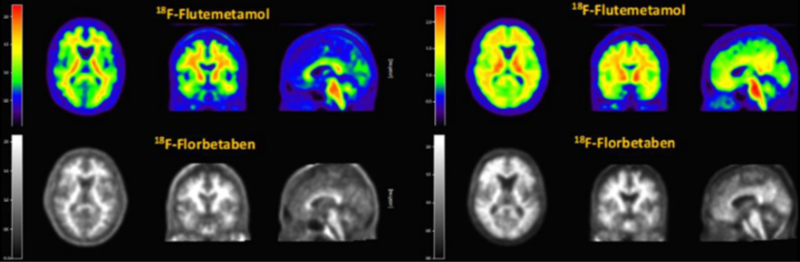

알츠하이머 치매 진단을 위해 쓰이는 '비자밀'(윗쪽 컬러 사진)과 '뉴라체크'(아랫쪽 흑백 사진) PET-CT 영상 비교 (자료=듀켐바이오)